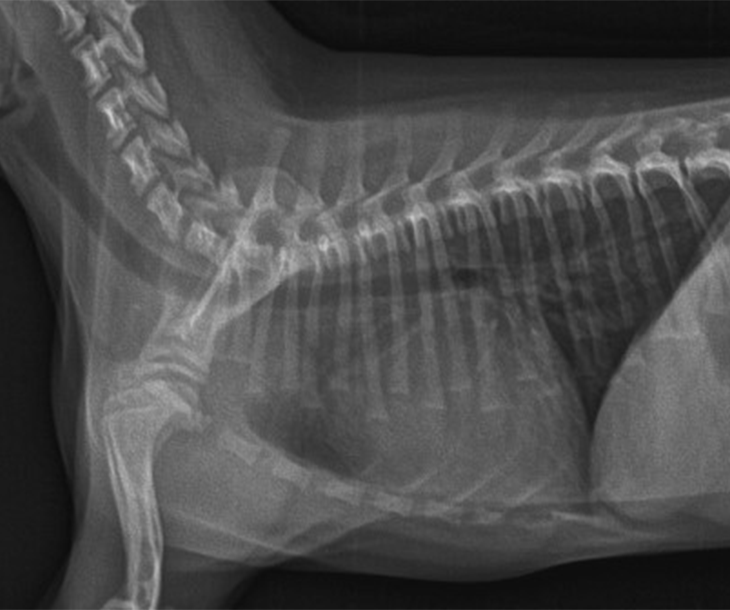

이첨판 폐쇄부전증

고령견에서 주로 발생하는 심장 질환 중 하나는 이첨판 퇴행증입니다. 이 질환은 심장의 이첨판에 퇴행적인 변화가 일어나며, 결과적으로 이첨판이 두꺼워지고 폐쇄 기능이 손실됩니다. 이로 인해 기침, 빠른 호흡, 운동 불내성 등의 증상이 나타날 수 있습니다. 이러한 증상은 심장 질환 외에도 다른 질환 에서도 나타날 수 있으므로 정확한 진단이 필요합니다.